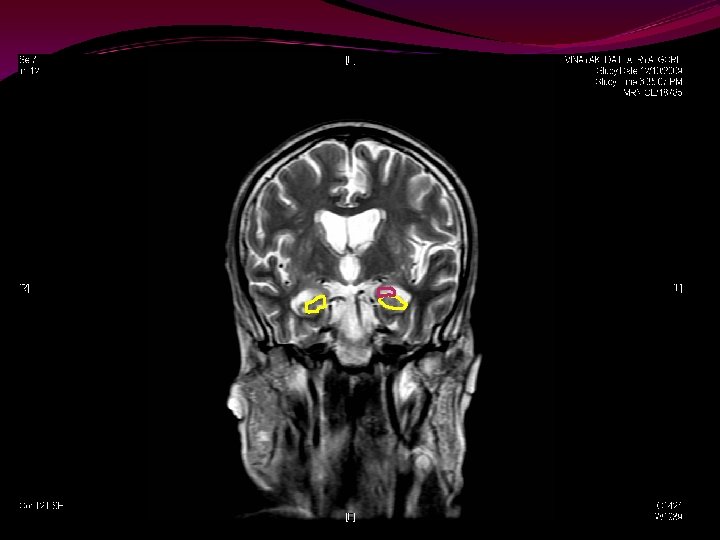

Hippocampus & Amygdala

Short term memory to long term memory. The Papez Circuit. Amygdala controls emotions, social inhibitions, aggression

Hippocampal atrophy is a highly sensitive indicator of incipient AD. It's evaluation by MRI volumetry provides entirely additional data to support the diagnosis. In contrast, simpler measurements or T 2 relaxometry provided only little diagnostic aid. The volume of the hippocampus correlated significantly with clinical severity assessed by MMSE, and with tests assessing delayed recall, which is considered to be affected early in dementia and may reflect hippocampal dysfunction. 2. The volume of the hippocampus is not significantly affected by normal aging. AAMI can be differentiated from dementia by hippocampal volumetry

Three-Dimensional Fast Spoiled Gradient-Recalled (3 D-SPGR) magnetic resonance imaging (MRI) Standard 1. 5 Tesla MRI Modified T 1 Post Contrast Contiguous Sections 2 mm – 1 mm thickness 256 x 256 grid